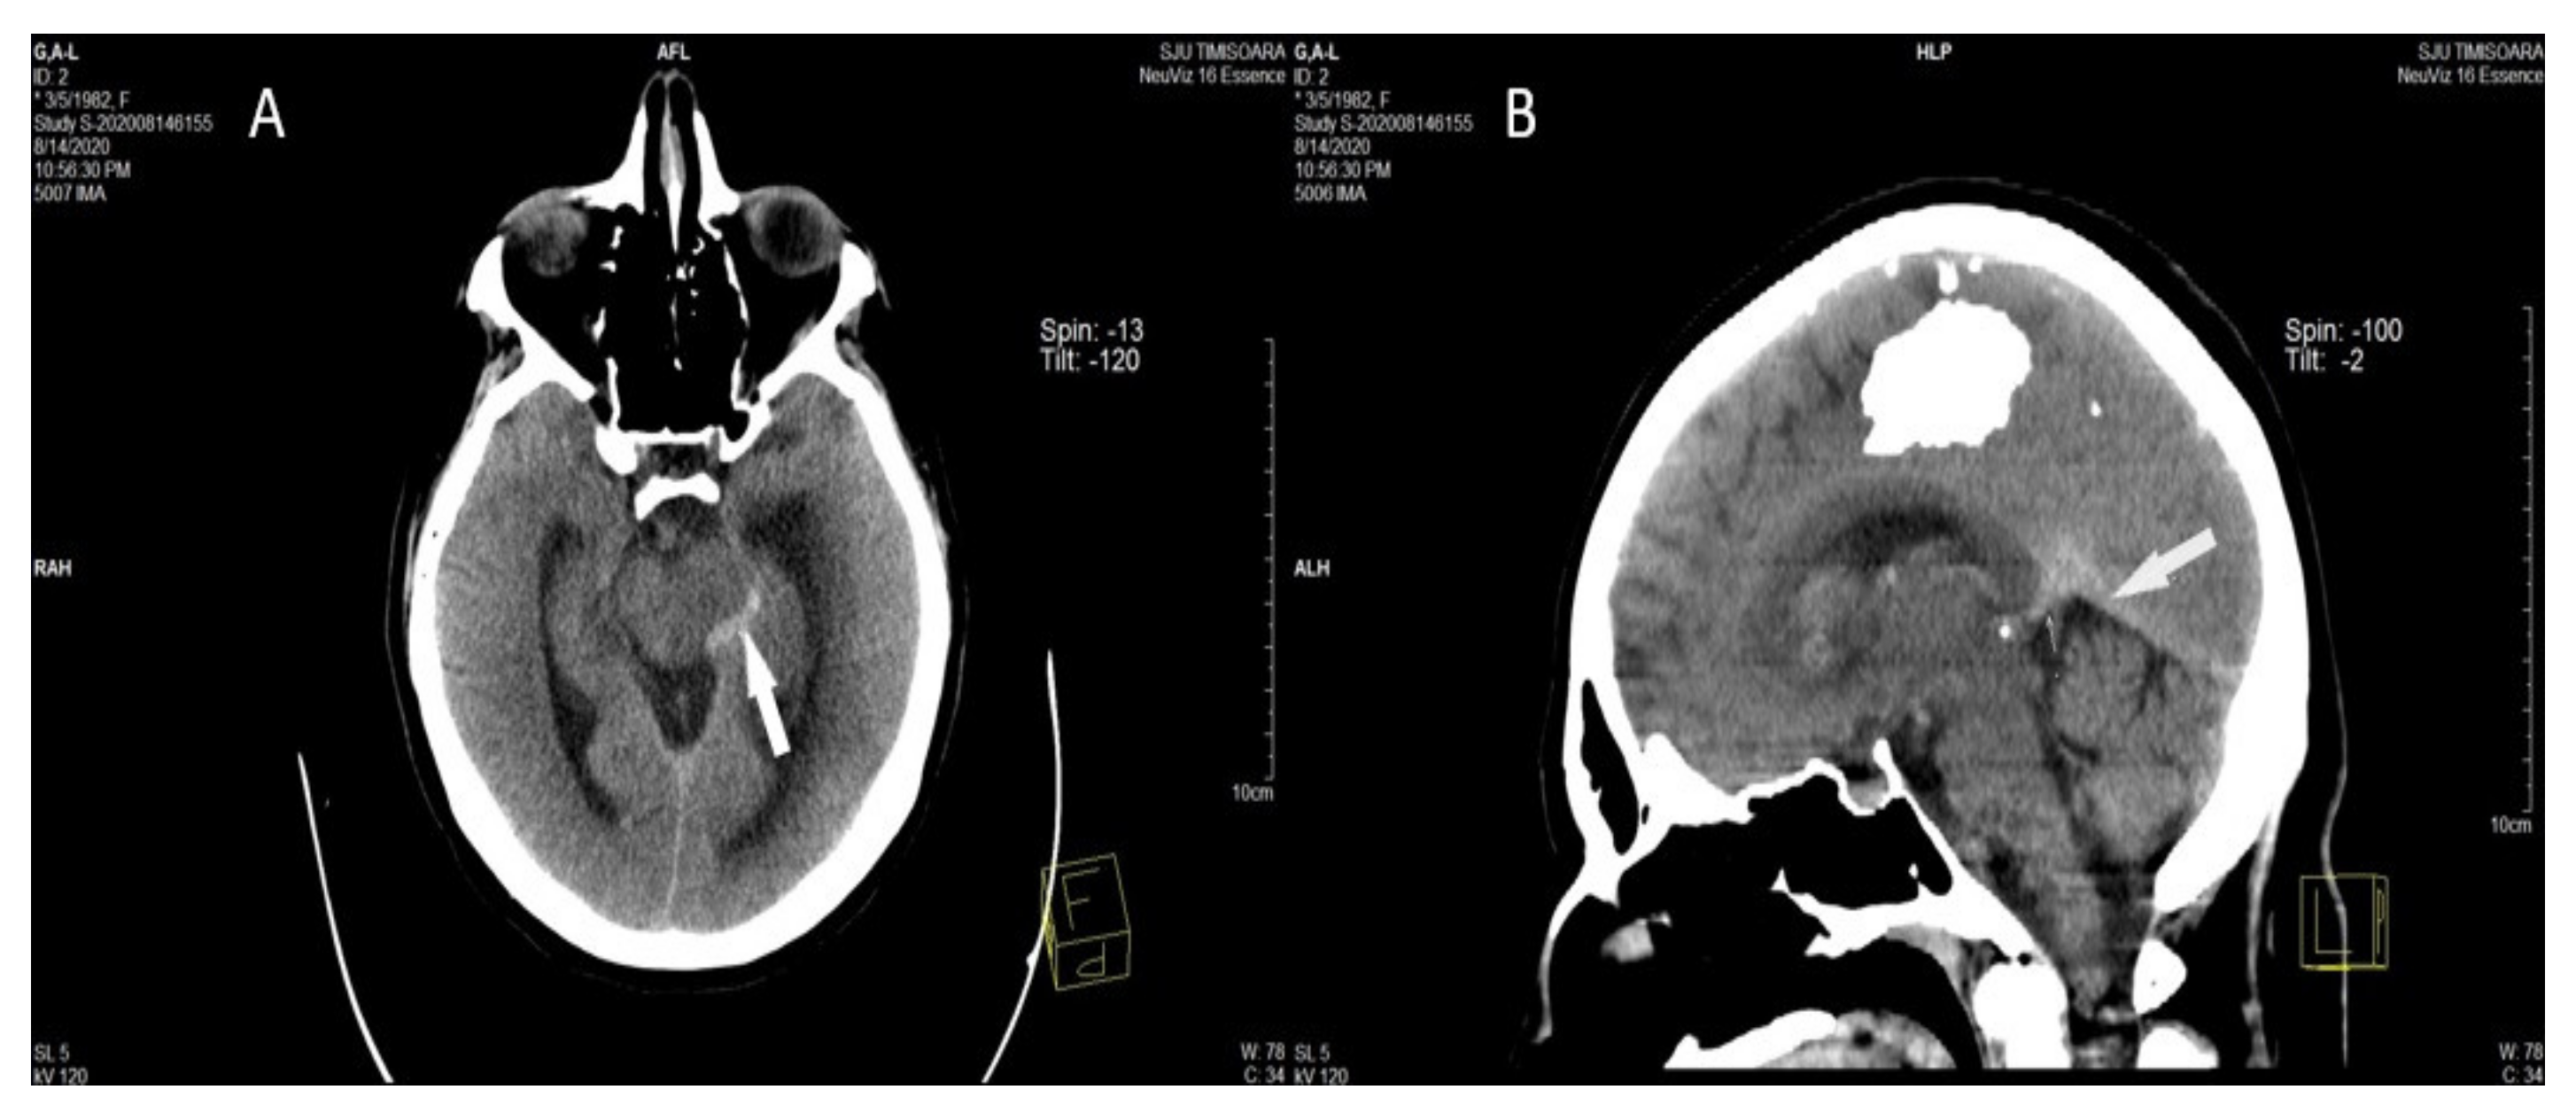

Direct Signs of CVT on Head CT

They represent the direct visualization of the venous clot inside the occluded cerebral vein, or dural sinus, and can be observed in about one-third of all CVT patients. They are the “cord sign”, the “dense triangle sign,” and the “empty delta sign” [6,74,79,80]. (Figure 3) [58].

Figure 3.

A, B. Axial (A) and MPR sagittal (B) non-contrast head computed tomography performed in the acute phase shows hyperdense appearance (acute thrombosis) of the left lateral mesencephalic [58].